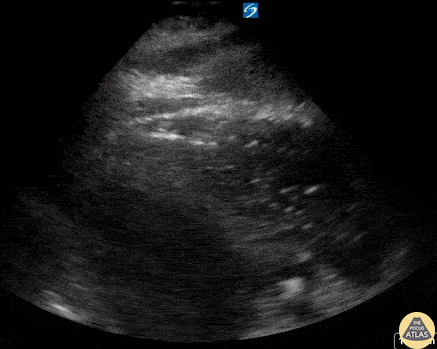

A 70 year old male presents 3 days post radiofrequency ablation for atrial fibrillation and atrial flutter. Presented to emergency department with evidence of septic shock, encephalopathy, and hypoxic respiratory failure. The above image shows evidence of air bubbles within the right atrium and ventricle, thought to be iatrogenic in nature after his recent cardiac procedure possibly due to necrotizing infection of the myocardium versus atriotracheal fistula or atrioesophageal fistula. The patient was placed in reverse Trendelenburg position (to mitigate potential embolus to cerebral venous circulation). Fortunately, following flight transfer to another facility, the intracardiac air was no longer visible on CT or echocardiography. Ian Keck